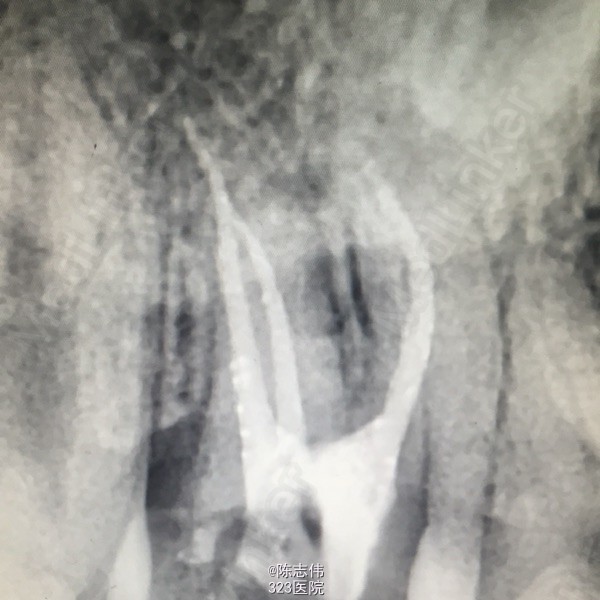

45远中龋损,探(+) 冷(+) 松动(-)

17,45缺损及髓,根尖无明显异常

17,45慢性牙髓炎

17,45RCT+桩+冠

处理:局麻下16,17,45去龋,16龋净未露髓,清理干燥隔湿后垫底+3M树脂充填。17,45揭开髓室顶,丁香油棉开放,降颌